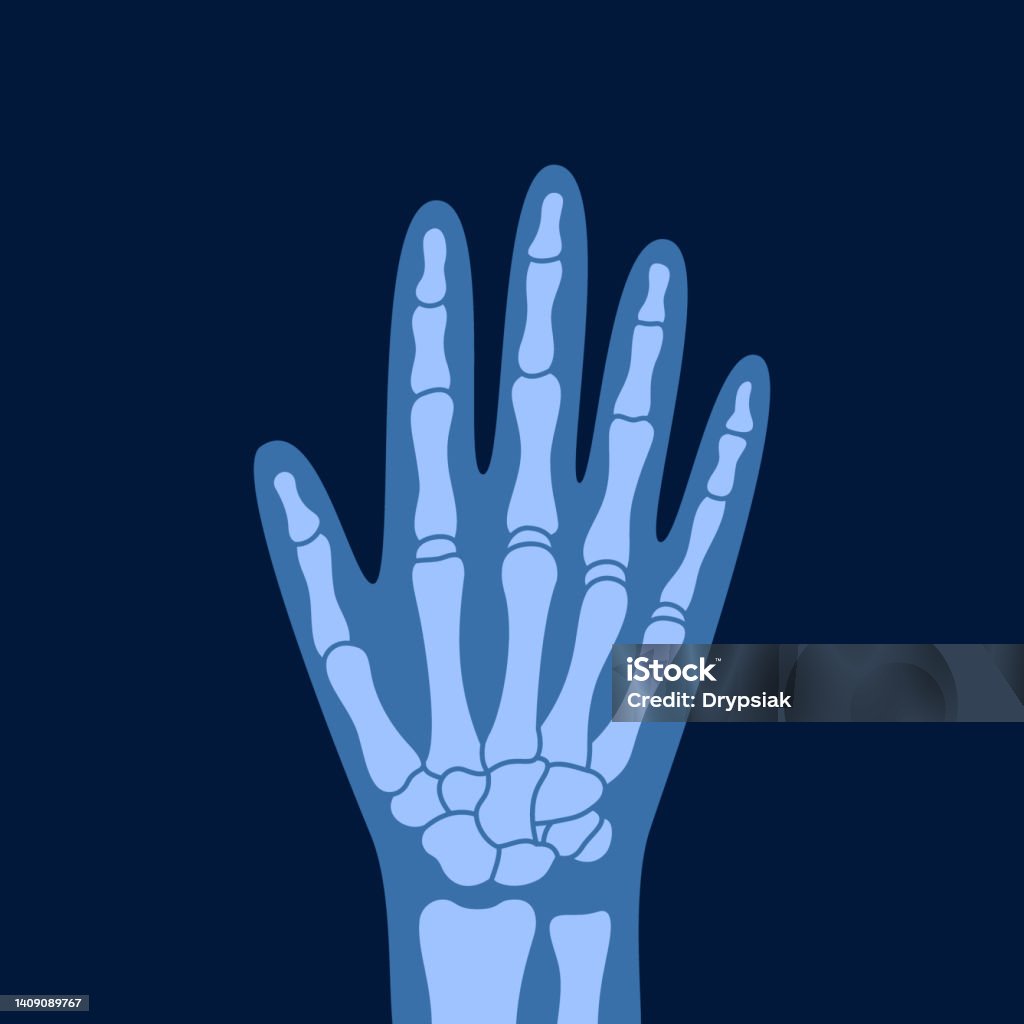

x-ray of a human hand